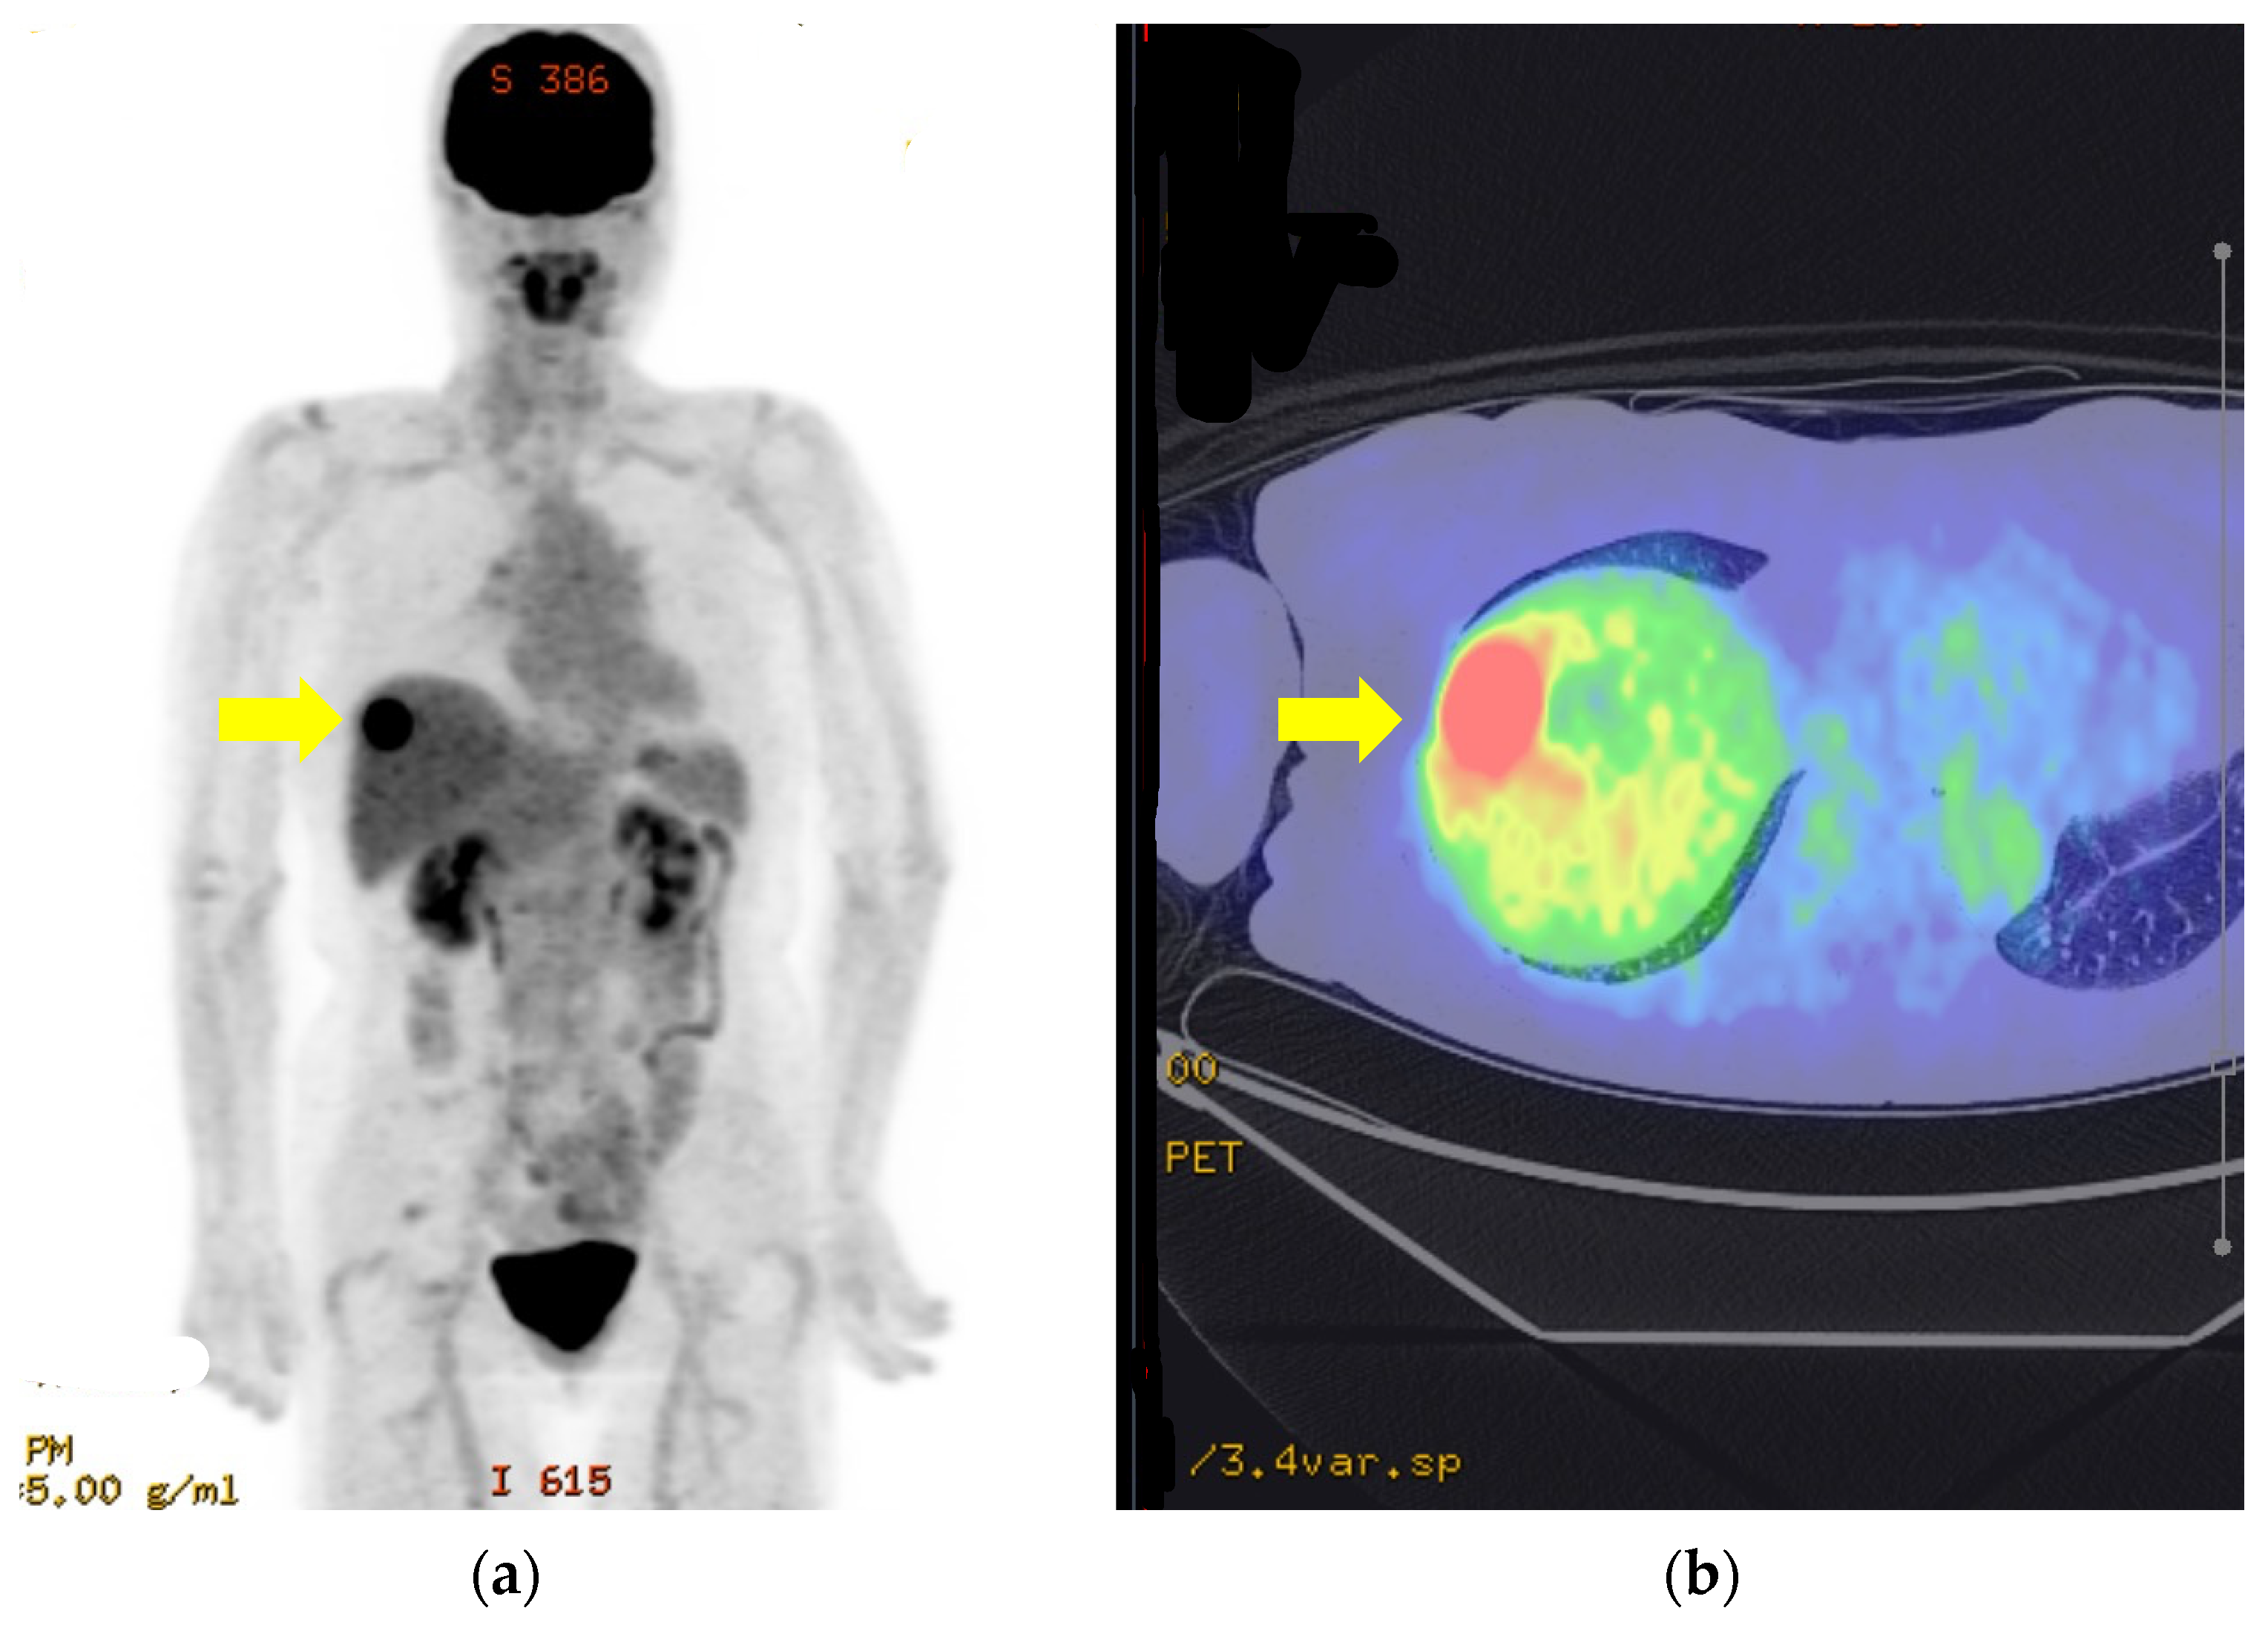

2. Case Report